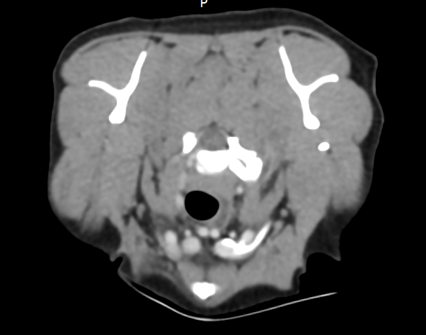

Denne godbiten har vi hatt på lager en liten stund, men vi har (heldigvis) hatt det travelt de siste ukene. Nå kommer endelig vårt nye kasus og vi vil gjerne benytte muligheten til å dele en fasinerende CT-studie som vi fikk inn fra Grong Dyreklinikk. Signalement: Blandingshund, hann, 8 år. Anamnese: Påkjørt for ca 5 år siden. Vondt høyre frambein og ble behandlet for fraktur i klobein. Hunden ble bedre, men så begynte han å halte på høyre frambein igjen. Klinisk mistenkes nerveskade.